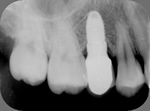

◆根管治療

むし歯等で歯の神経が死んでしまった場合に必要となる根の治療です。

根管治療X線写真